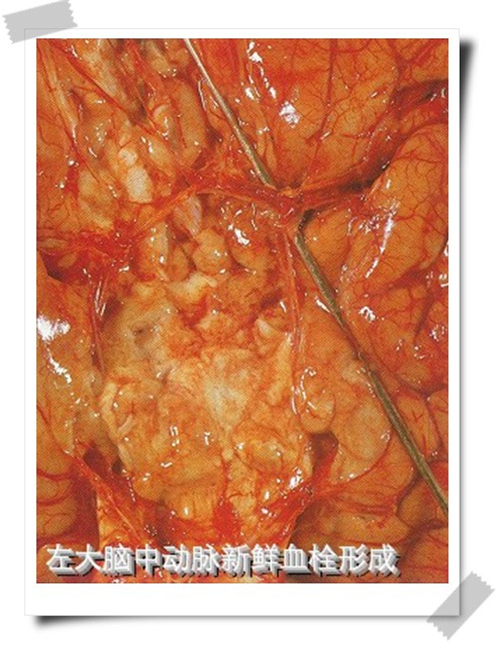

左大腦中動脈栓塞腦梗塞